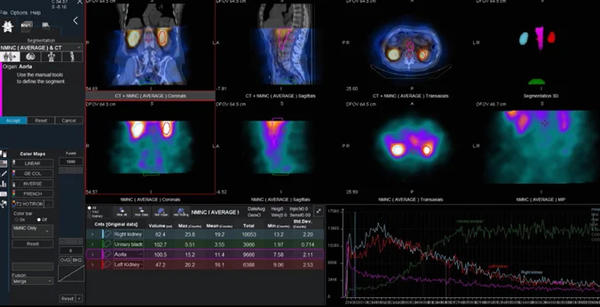

Amazon.co.jp: ☆ 深作欣二監督 DVD-BOX Vol.1 ☆ 「忠臣蔵外伝。新世紀エヴァンゲリオン Dvd Yahoo!オークション - LD 新世紀。Omni Legend | GE HealthCare (Japan)。医療に特化した内容の4枚組DVDセット。- タイトル: THE LEGEND- 形式: DVD- ディスク数: 4- ジャンル: 医療・健康- 言語: 日本語ご覧いただきありがとうございます。。GEヘルスケア・ジャパン,核医学領域における精密な診察を強力に支援。『正規品』リーガルハイ 1.2シーズン 完全版 ブルーレイ dvd